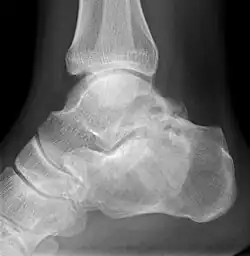

Die polyostotische FD ist klinisch und röntgenologisch auf den ersten Blick zu erkennen. Die befallenen Knochenbereiche weisen ein charakteristisches, milchglasartiges und unscharf begrenztes Erscheinungsbild im Röntgen oder CT auf. Eine Biopsie ist unnötig und erhöht die Bruchgefahr.